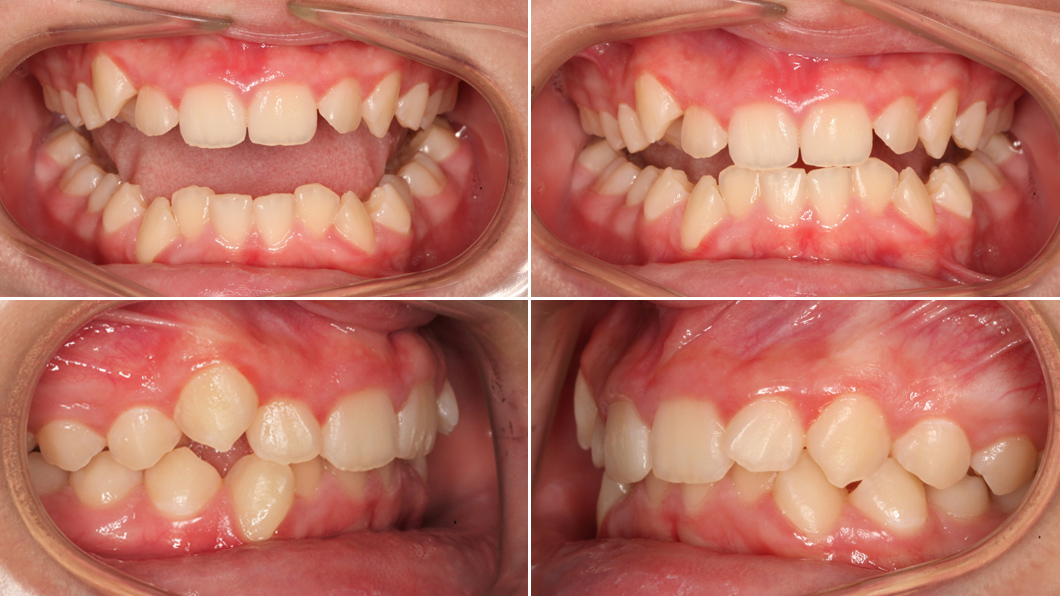

Пациент: В., 11 лет

Врач: Якушенков Владислав Викторович, врач-стоматолог, ортодонт

Причина обращения пациента: скученность зубов, выпирающие резцы, начавшаяся патологическая стираемость нижних зубов

Особенность: лечение в сменном прикусе (у ребёнка ещё есть молочные зубы) с целью профилактики

Папа привел В. на консультацию с типичной жалобой на неровные, скученные и выпирающие вперёд зубы. Однако внимательный осмотр выявил куда более серьёзную проблему: на резцах нижней челюсти уже были заметны признаки патологической стираемости эмали.

Почему это произошло у ребёнка? Причина часто кроется в неправильном прикусе. Диагноз В. – выраженная скученность. Когда зубам тесно, они занимают неправильные позиции, и некоторые из них (чаще всего выступающие вперёд нижние резцы) начинают принимать на себя более сильную нагрузку, для которой не предназначены. Иногда к этому добавляются и психологические факторы, усугубляющие проблему.